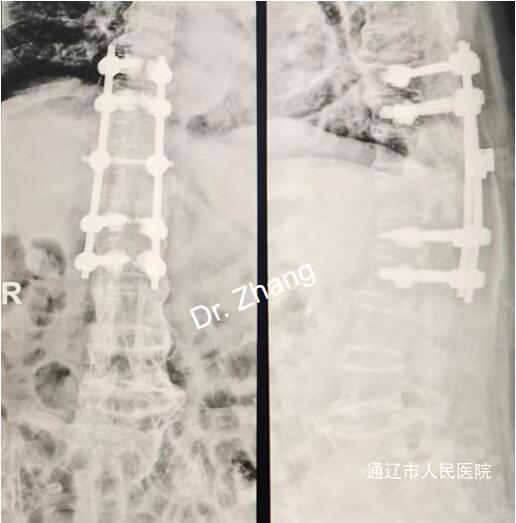

面对手术难度大、麻醉风险高、术后康复难等挑战,脊柱外科联合西院手术麻醉科、西院ICU等开展MDT多学科会诊,最终制定"骨水泥强化螺钉固定术"方案,通过精准的置钉技术稳定骨折椎体,同时优化围手术期管理。实现术后患者恢复远超预期,术后3天佩戴护具坐起,1周自主行走,顺利出院。为此,患者家属手写千字感谢信,盛赞团队"以精湛技术打破高龄手术禁区"。

2、骨骼"豆腐渣"难题:重度骨质疏松使螺钉把持力极差,传统内固定易失效,需结合骨水泥强化技术。